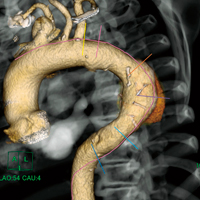

中心軸は,ストレートCPRやストレッチCPR,3D VRなどさまざまな画面上にて自在に修正することができる。CPR画面上のフリーハンドでの中心線修正も本ソフトウェアでは可能である。実際のステントグラフトが挿入された状態に近い軸を想定し計画を作成したり,大彎側に沿った解析軸に修正したりすることが容易であり,実際のステントグラフトが留置される範囲を予測する際などにも有用である(図3)。

図3 3D VR大動脈大彎側へ修正された解析軸